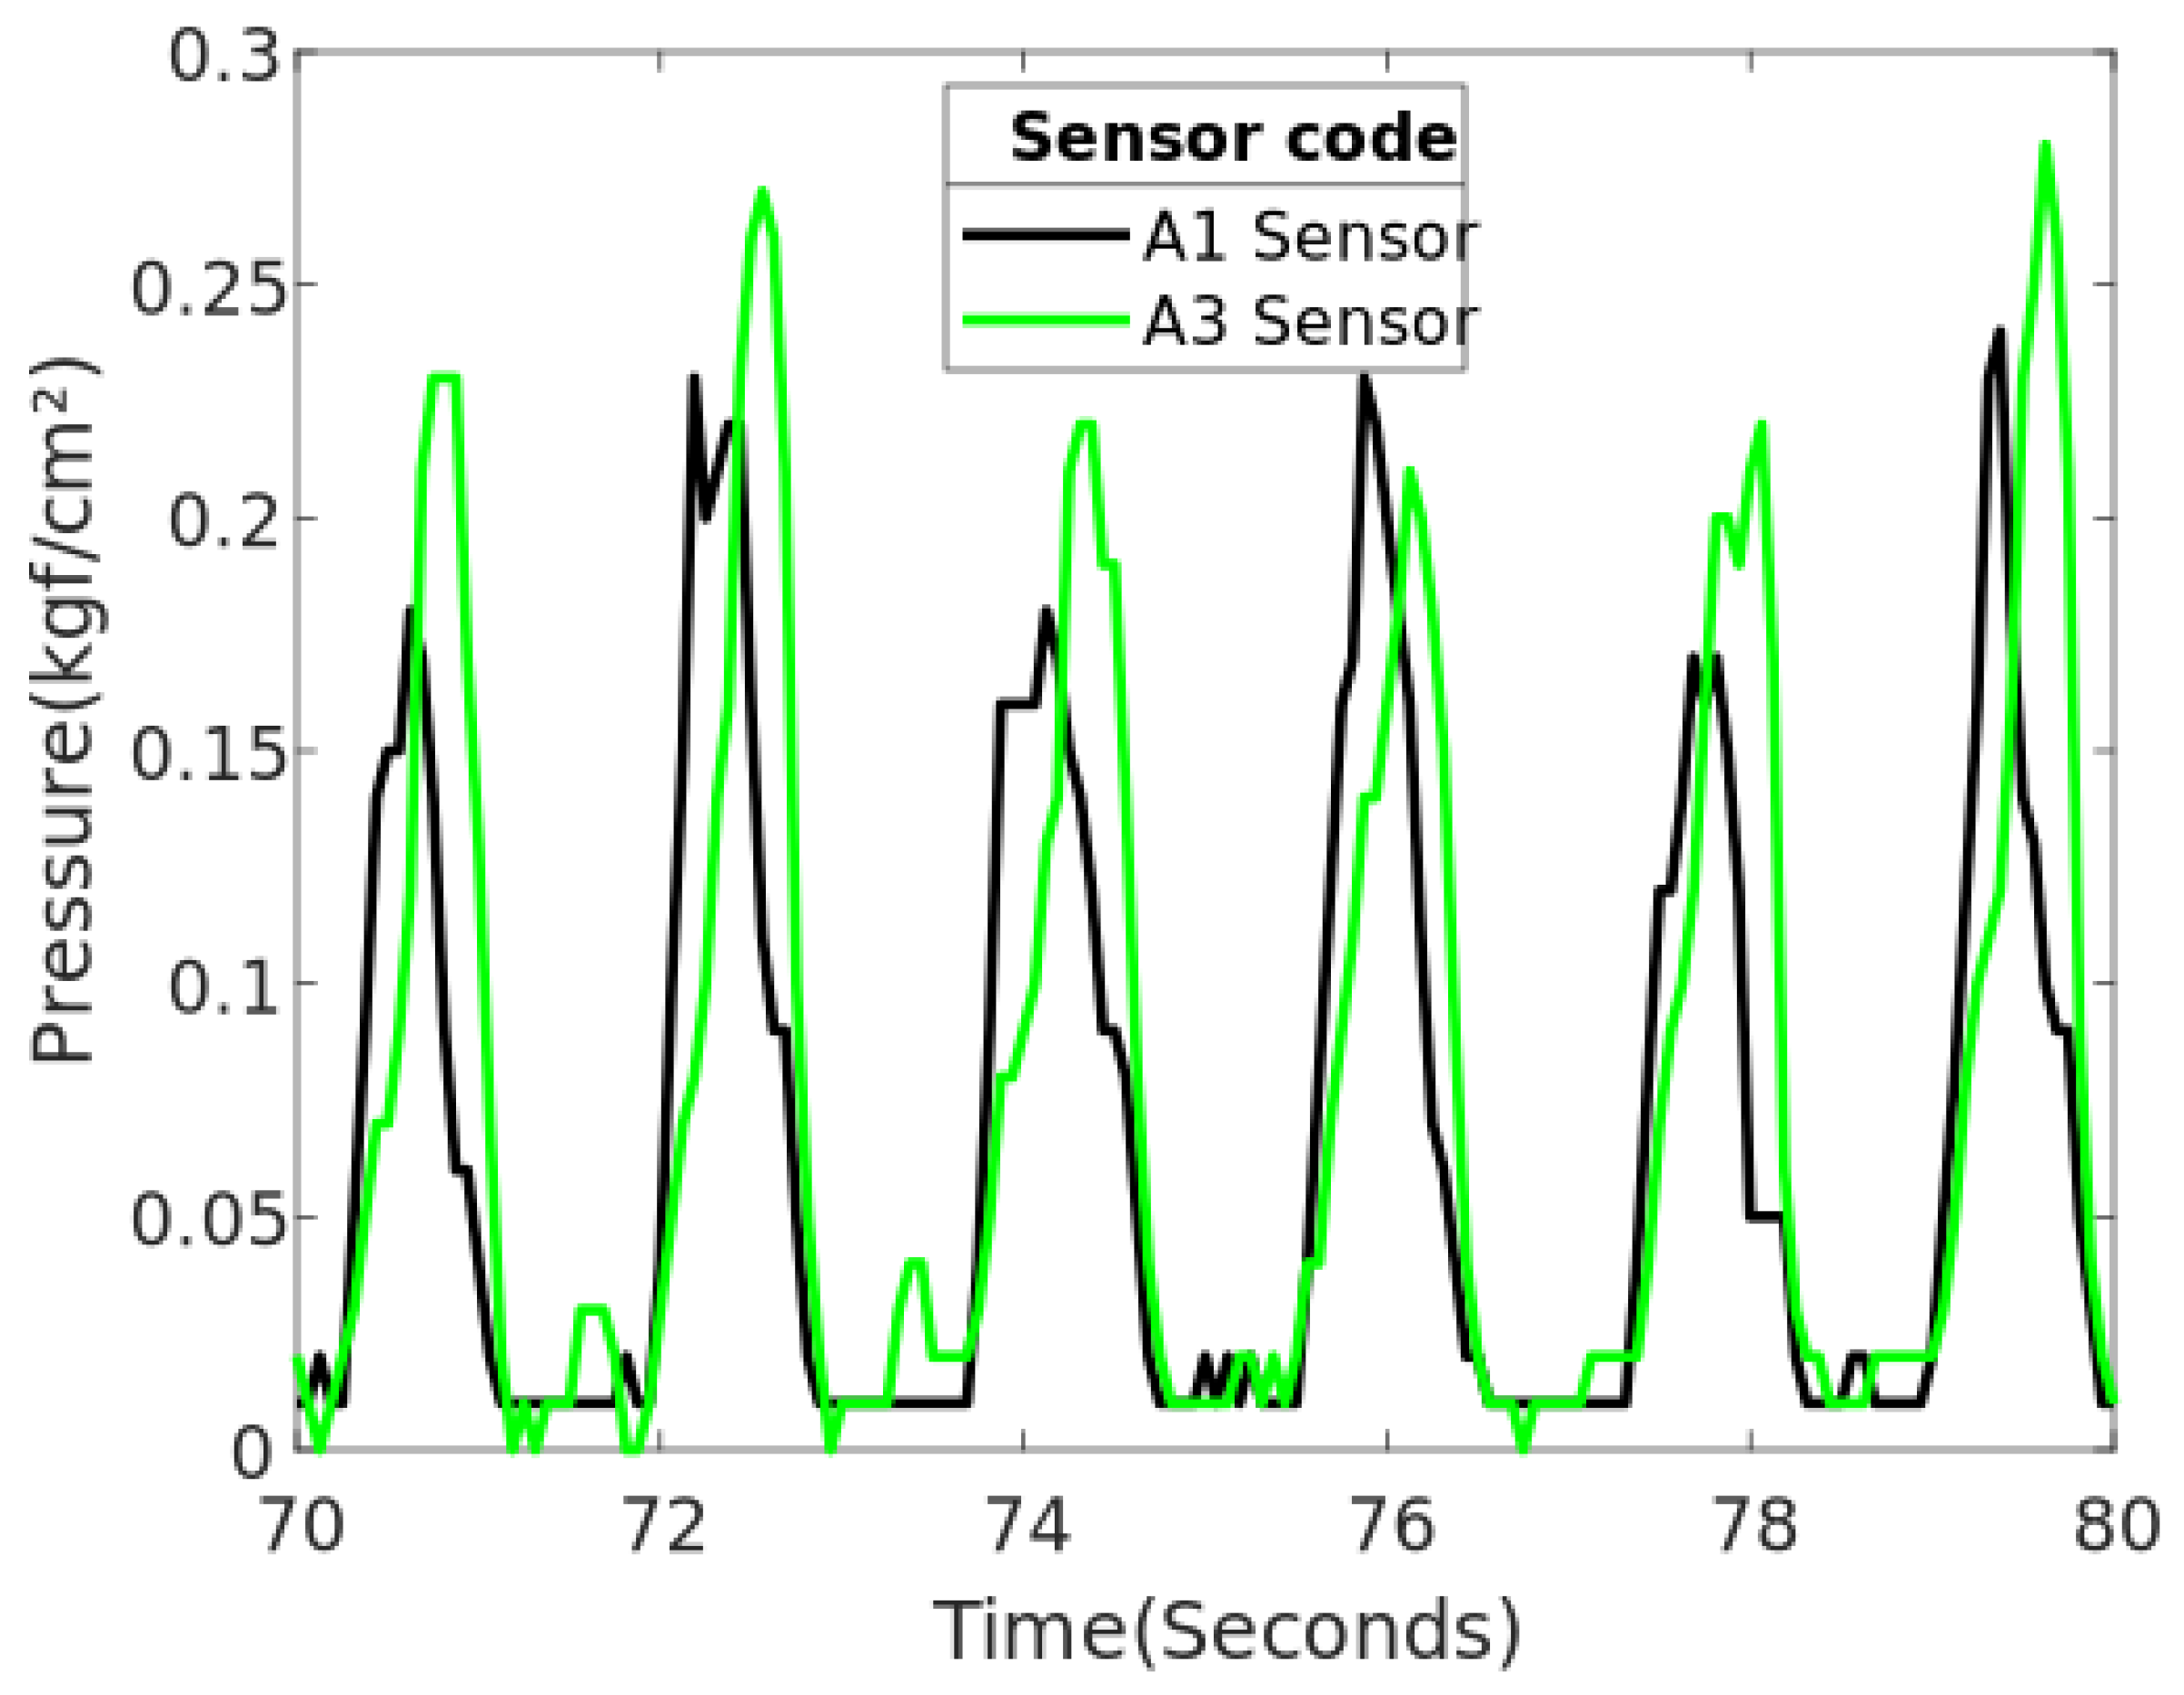

3.3. SIFP System Test